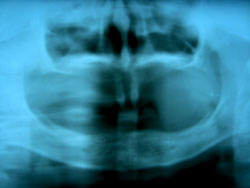

Một trong những điều lo lắng nhất của thân nhân bệnh nhi là tình trạng mọc răng của con em mình, vì sao trong miệng trẻ chỉ có vài cái răng hoặc không có cái răng nào? Liệu rằng sau này trẻ có mọc răng đầy đủ không? Để giải đáp các thắc mắc trên, chúng ta cùng xem các hình ảnh dưới đây về tình trạng răng trong miệng và hình ảnh X Quang răng:

Hình trên phim XQuang |

Như vậy, bệnh này làm trì hoãn sự mọc răng vĩnh viễn, cũng như không có mầm răng trong xương hàm